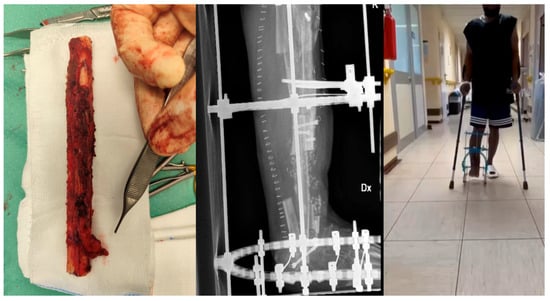

Management and Treatment Strategies for Distal Tibia and Ankle Infections: Our Clinical Experience

by Antonio Mascio, Chiara Comisi, Carmen Barlotti, Tommaso Greco, Federico Moretti, Virginia Cinelli, Andrea De Fazio, Giovan Giuseppe Mazzella, Giulio Maccauro and Carlo Perisano

Background: The management of infections involving the distal tibia and ankle is a significant challenge in orthopedic surgery due to complex anatomy and the high risk of complications. The study aims to present our clinical experience in managing these infections and focusing on [...] Read more.

Background: The management of infections involving the distal tibia and ankle is a significant challenge in orthopedic surgery due to complex anatomy and the high risk of complications. The study aims to present our clinical experience in managing these infections and focusing on surgical strategies, infection control, and functional outcomes over a minimum 24-month follow-up period. Methods: This is an observational, retrospective case series of 17 patients treated for osteoarticular infections of the distal tibia and/or ankle between January 2020 and May 2023, in a second-level referral trauma center. A staged surgical approach was employed, including radical debridement, temporary stabilization with external fixation, and, in most cases, implantation of a cement spacer loaded with antibiotics. Functional outcomes were assessed using scores such as EQ-5D-5L. Results: The cohort was predominantly male (76.5%), with a high prevalence of elevated BMI and comorbidities. Infection onset was most frequently associated with open fractures (64.7%). Staphylococcus aureus was the most common isolated pathogen (41.2%), and infections caused by Gram-negative or multidrug-resistant bacteria were associated with more reoperations. Overall, complications occurred in 10 patients (58.8%), requiring reintervention in 9 patients (52.9%). Limb salvage was achieved in 16 of 17 patients (94.1%). Conclusions: Our study highlights the critical role of a tailored, multidisciplinary approach in managing these complex infections. Meticulous surgical planning and proactive management of complications are essential for optimizing patient outcomes. Full article